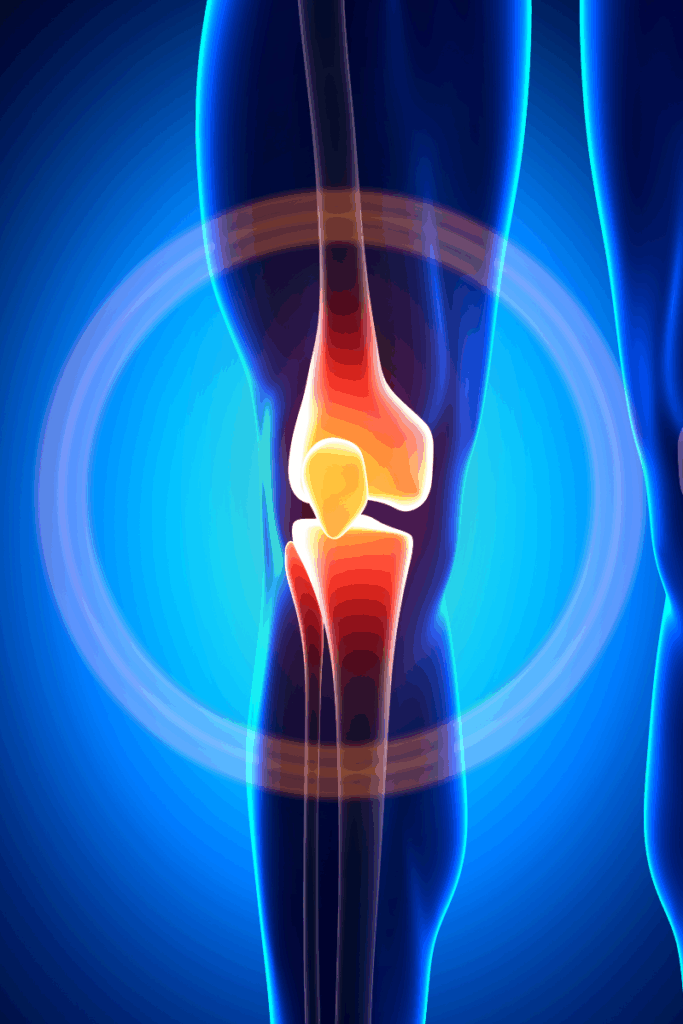

Wondering how long knee replacement recovery really takes? You’re not alone. Knee replacements are increasingly common, and so are the questions that come with them—especially around healing time, physical therapy, and what to expect after surgery.

We know—“it depends” isn’t the most satisfying answer, but it’s the most honest one. Recovery from a total knee replacement typically takes 3 to 6 months, while some patients may need up to 12 months to feel fully recovered. On the other hand, those undergoing a partial knee replacement may recover faster.